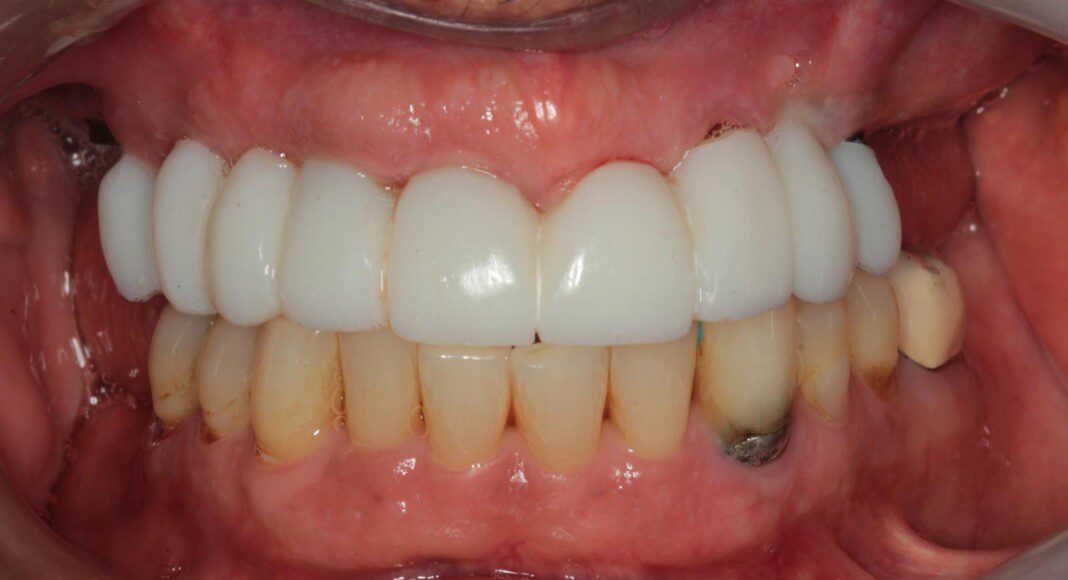

Immediate temporary bridge in place on day of surgery. Note the tissues are barely disturbed. No bone or soft tissue removal.